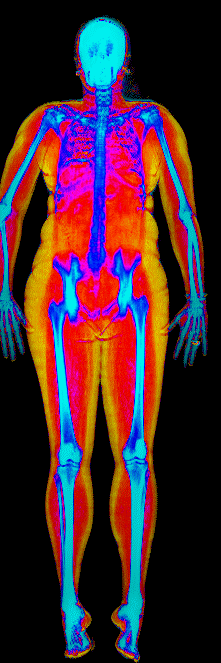

This page features real, anonymized DEXA scan images from BodyStats clients, organized by gender and body fat percentage in 5% increments. DEXA (Dual-Energy X-ray Absorptiometry) is the clinical gold standard for measuring body composition — far more accurate than scales, calipers, or visual estimates.

Each colorized scan shows the distribution of fat tissue (shown in warmer colors) and lean tissue (cooler colors) throughout the body. Compare your own DEXA scan to others in your range, or see what different body fat levels actually look like on a scan.

Female DEXA Scans by Body Fat %

25 to 30% body fat